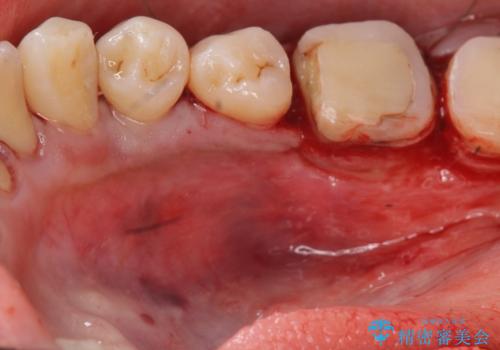

奥歯は既に根管治療が為されクラウンを装着する必要性がある状態ですが、歯の高さが低くクラウンの安定性・強度を担保するために歯周外科を行う治療計画としました。

歯周外科を行うことで、歯ぐきの位置を下げ歯の高さを作り出し安定したクラウンの装着が可能となります。また同時に舌の邪魔となっていた骨隆起の除去を行うこととしました。